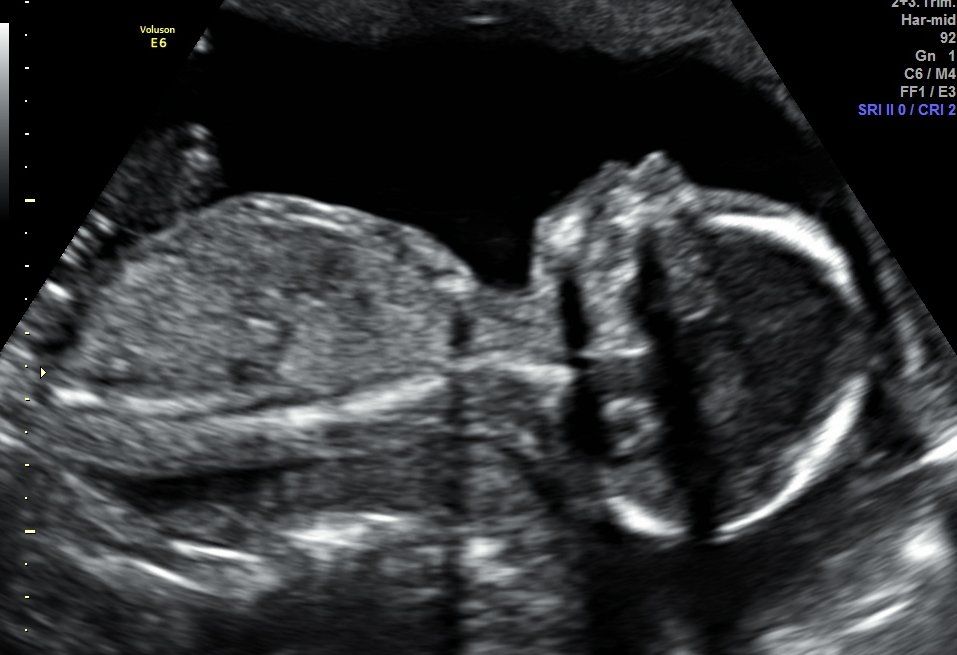

Imagen 8K ¿Qué es?                                                                                                        La imagen 8K es una técnica novedosa que aporta mayor sensación de realismo a las imágenes que se obtienen mediante la adquisición de ecografía 5D que, ya de por sí, resulta ser una técnica ecográfica hiper-realista.                                 Dicha técnica suaviza y texturiza las imágenes obtenidas, aumenta los contrastes y se incorporan detalles que aumentan, si cabe, la sensación de realismo. A petición del cliente la imagen seleccionada es procesada y entregada durante los días posteriores a la realización de la ecografía 5D.                                 En Centre Miramed estamos orgullosos de poder poner a disposición de nuestros/as clientes/as la técnica 8K como ejemplo de vanguardia y crecimiento continuado.